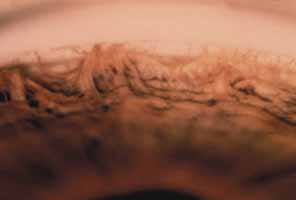

Anomalous Iris Vessels

Vascular anomalies of the iris can present as persistence of the tunica vasculosa lentis or as irregularly wandering superficial anomalous iris vessels. The first condition exhibits a regular arrangement of vessels looping into the pupillary axis in front of or behind the lens. Normal radial vessels on the iris surface are also prominent be-cause there is usually hypoplasia of the anterior iris stroma.

In the second condition, anomalous superficial iris vessels wander irregularly over the iris surface with an often distorted pupil (Fig. 4). The iris surface has a whorled appearance and the anterior iris stroma is often hypoplastic. These vascular anomalies differ from the normal exposure of radial iris vessels seen in lightly pigmented eyes. Anomalous iris vessels are seen most frequently in eyes that present with glaucoma and cloudy corneas at birth, and are not associated with any particular syndrome. It is unclear whether they represent an earlier onset of primary congenital glaucoma or an entirely different syndrome. They do indicate a more severe malformation of the anterior segment and a grave prognosis, with such cases requiring multiple surgeries.

Fig. 4 Anomalous iris vessels. Vessels course irregularly over the iris surface. On the right, small vessels are seen crossing the pupillary margin. The pupil is distorted at the 10 o'clock position. Radial iris fibers are curved and irregularly arranged.